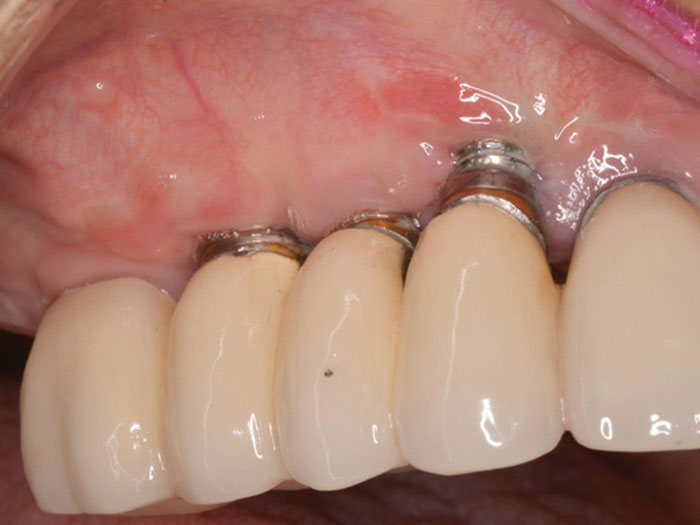

Hình ảnh khách hàng trồng răng implant tại Nha khoa SV quận 3